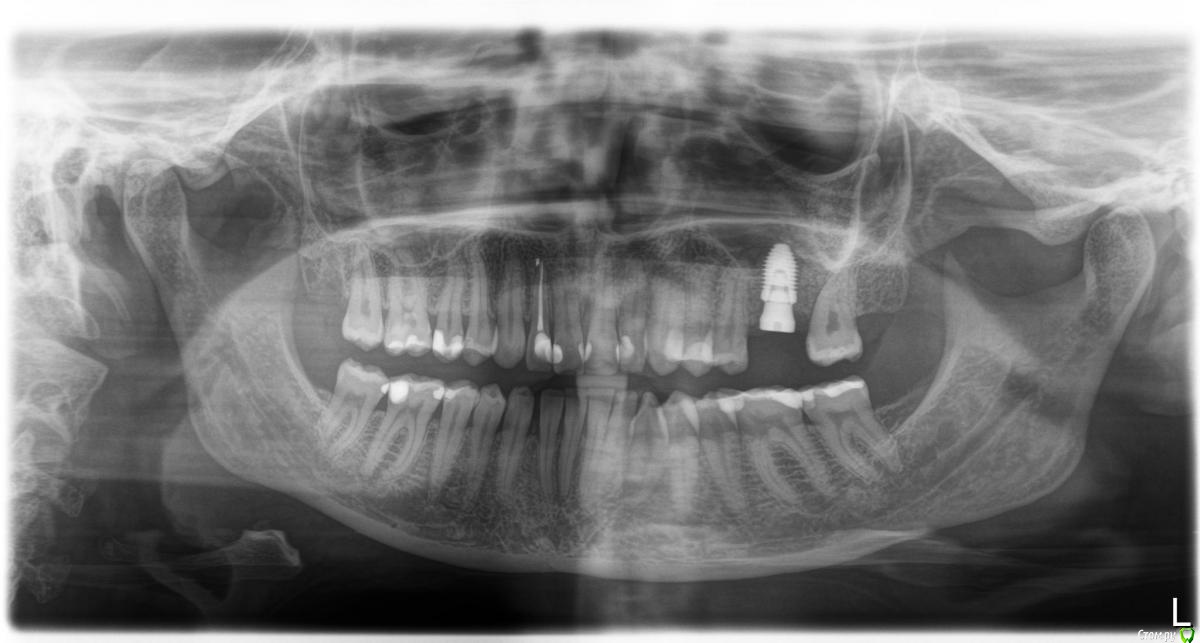

sole13 Опубликовано 26 апреля, 2018 Поделиться Опубликовано 26 апреля, 2018 посоветуйте, пожалуйста недавно удалили 26 зуб. КТ на дату 14 апреля (2, 5 месяца после удаления). Насколько я понимаю, в среднем у меня 6 мм кости. Возможен ли в моем случае закрытый синус лифтинг (а не открытый) и имплант 9 на 5 мм будет достаточен ?( высота и ширина) про достаточность - подразумевается, что конструкция будет выдерживать жевательную нагрузку на протяжении многих лет и при протезировании не будет "лошадиной" коронки. спасибо! Ссылка на комментарий

sole13 Опубликовано 5 мая, 2018 Автор Поделиться Опубликовано 5 мая, 2018 (изменено) уважаемые врачи, спасибо за мнения! решила выложить 3-4 снимка до финального момента,возможно, это будет полезно другим пациентам.------------------ вчера была имплантация, в силу моих ограничений временных был доступен врач,практикующий на Нобеле, поэтому с астрой и рекомендациями не сложилось установлен нобель коникал конекшен (pmc) 10 на 5 мм с закрытым синус лифтингом и формирователем сразу же. назначены стандартные антибиотики и противоотечные.на втором этапе через 3-4 месяца договорились решить про десневую пластику,далее временная коронка на 2-3 месяца и постоянная.врач говорит что скорее всего коронка будет выше остальных,но я надеюсь на десну и незаметность. пластику кости доктор, к сожалению, сказал что не сделает в моем случае одномоментно остео синтетическими материалами,только долго и дорого с куском своей кости и т д. перед началом операции врач предупредил что 50 на 50 закрытый или открытый синус, удалось с закрытым в моем случае. вся операция длилась 25 мин: сначала разрезали,потом посверлили ,потом постучали молотком, потом еще посверлили, потом попросили надуть щеки с зажатым носом,чтобы проверить отсутствие перфораций,потом имплант, формирователь и сами швы. потом снимок и принудительно 2 укола внутримышечно дексометазон и антибиотик, лед в руки и отпустили домой. Изменено 5 мая, 2018 пользователем sole13 1 Ссылка на комментарий

sole13 Опубликовано 10 августа, 2018 Автор Поделиться Опубликовано 10 августа, 2018 (изменено) уважаемые хирурги, прошу ваш совет 3 месяца назад было сделана имплантация 26 зуба, закрытый синус,сделано повторное свежее КТ через 3 месяца у меня ощущение постоянного комка слизи в носоглотке с момента операции (иногда отплевывается часть и это оч густое содержимое). пила 2 курса синупреда, 2 месяца на море, 2 курса ринофлоимуцила прокапала. если чуть заболеваю, то слева ощущение тяжести в крыле носа как при гайморите. хирург говорит, что перфорации гайморовой нет и в 50% случаях это нормальная реакция гайморовой - выделять слизь, что через месяца 3-4 у меня это пройдет. действительно гайморова пазуха не перфорирована и ощущение слизи -норма? еще меня смущает черная область вверху импланта справа на снимке и черное под имплантом и справа по вертикали - что это? Изменено 10 августа, 2018 пользователем sole13 Ссылка на комментарий

Neilrus Опубликовано 10 августа, 2018 Поделиться Опубликовано 10 августа, 2018 и я бы еще обратил внимание на 24 зуб, срезы бы посмотреть Ссылка на комментарий